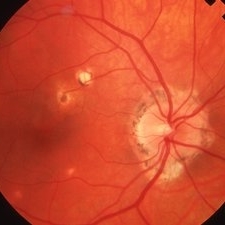

Histoplasmosis

Histoplasmosis

Mar 27 2019 by Gary R. Cook, MD, FACS

24-year-old white female with presumed ocular histoplasmosis (POHS) demonstrating minimal peripapillary atrophy but 3 atrophic histo spots around the optic nerve of her left eye; patient was asymptomatic; V.A.= 20/20.

Imaging device: Topcon VT-50

Condition/keywords: atrophic spot, ocular histoplasmosis syndrome (OHS), presumed ocular histoplasmosis syndrome (POHS)